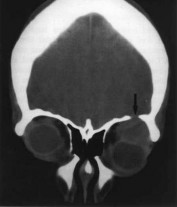

Hình 1.4. Cắt lớp vi tính u hỗn hợp tuyến lệ

Mắt trái có hiện tượng mòn xương trần hốc mắt Nguồn: Parks và cộng sự (1990)38